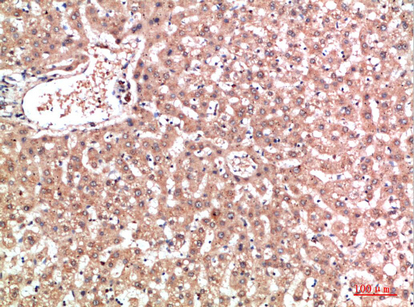

IHC 1/50-300 Human,Mouse,Rat